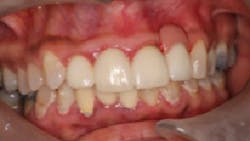

The patient presented to restore the implant six months later with a predicted large vertical and horizontal tissue defect (figure 3). The implant was restored with gingival ceramics to compensate for the ridge defect (figure 4).

The patient was very pleased with the final outcome (figure 5), even though this case certainly would not be considered an esthetic success. Because of the patient’s concerns and low smile line (figure 6), this case was completed six months postextraction and in a cost-efficient manner.